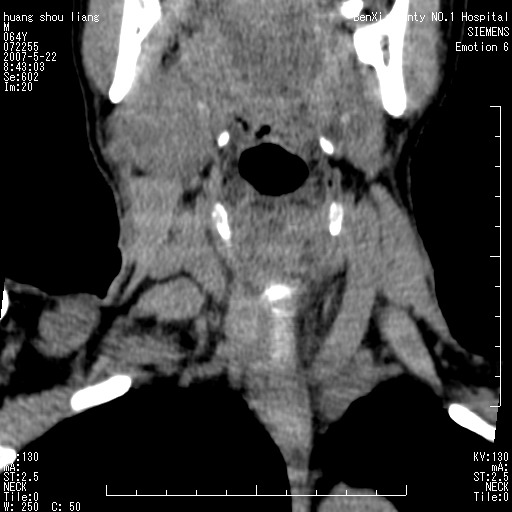

男性,64岁。颈部包块8年。最近增大。

对不起大家,可能是片子发太多有点乱,正常腮腺在下颌角的外侧,颌下腺在下颌体的中部内侧,本例在下颌角内侧偏下,和腺体一点关系都没有,从vrt和mpr上可以很明显看出来,再者肿块是好多粘连在一块的,大家在仔细看看,左侧可能也是吧,我还是考虑为肿大的淋巴结融合在一块,但性质??????

右侧腮腺下部均匀软组织密度肿块,外形不规则,与周围组织分界清晰,考虑右侧腮腺混合瘤或多形性腺瘤。

大家好,病理结果出来了,如大家所说,颌下腺混合瘤。

唉,解剖没学好吧,我诊断错了,不过还是有些不理解回去我在多看看书,谢谢大家的参与,以后我还会奉献好的病例。